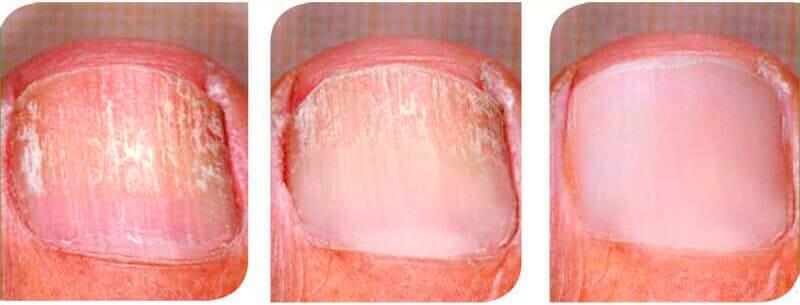

Das Produkt kann Nagelpilze vollständig zerstören, indem die äußeren Symptome entfernt und der gesamte Körper gereinigt werden. Schon ab dem ersten Tag reduziert das Mittel das Risiko des plötzlichen Todes auf quasi 0%. Durch die Verwendung dieses Mittels können Betroffene aufatmen. Der Blutkreislauf sowie die inneren Organe werden von den Pilzzellen befreit, sodass die Infektion, die sonst langsam bis zum Tode geführt hätte, abklingt.

Exodermin hilft dem Körper dabei, spezielle Antikörper zu produzieren, die den Pilz im gesamten Körper zerstören. Dadurch ist der Körper in der Lage, den Pilz loszuwerden. Die Produktion der Antikörper wird übrigens auch dann fortgesetzt, wenn das Mittel nicht mehr verwendet wird. Dadurch wird die Reaktion auf die Pilze um das Zehnfache erhöht und eine erneute Infektion gilt quasi als ausgeschlossen. Mit nur einer einigen Behandlung ist Exodermin in der Lage, Pilzinfektionen zu beseitigen und Komplikationen zu verhindern.

Exodermin neutralisiert die Infektion, indem die Pilzpartikel im Blut und in den inneren Organen zerbrochen werden. Dadurch kann sich die Infektion im Körper nicht weiter ausbreiten, was zu einer vollständigen Genesung führt. Sämtliche Spuren der Infektion werden beseitigt und der Patient kann wieder ein gesundes Leben führen. Der Körper entwickelt zudem eine Immunität gegen die Pilze, wodurch keine erneute Infektion möglich ist.

1. Sie zerstört die Pilzinfektion.

2. Sie lindert schon ab der ersten Anwendung den Juckreiz und die Irritationen der Haut.

3. Sie regeneriert schnell die Nägel und heilt die Wunden und Risse.

SIe lindert sämtliche Symptome der Pilzkrankheit innerhalb der empfohlenen Anwendungsdauer.

Mein Mann hat 3 Jahre lang unter einer Pilzinfektion gelitten und es war ein richtiger Albtraum. Seine Nägel waren richtig creme und der Geruch war furchtbar. Als erstes probierte er ein paar Tropfen und danach einen Lack. Ich kann mich nicht mehr genau an die Namen erinnern, aber sie haben nicht geholfen. Er wollte schon aufgeben, doch dann hat ihm ein Freund Exodermin empfohlen. Schaut euch nur mal an, was er damit nach nur 4 Wochen erreicht hat.